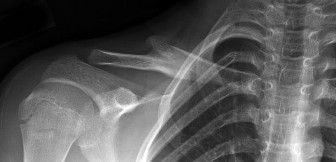

A 12-year-old elite Little League pitcher complains of progressively worsening pain in his throwing shoulder during the late cocking phase. Radiographs show widening and sclerosis of the proximal humeral physis. What is the primary pathophysiology of this condition (Little League Shoulder)?

A 9-year-old male presents with acute shoulder pain after throwing a baseball. Radiographs reveal a pathologic fracture through a centrally located, lytic, expansile bone lesion in the proximal humeral metaphysis. A "fallen leaf" sign is noted. What is the most appropriate initial management?

A 14-year-old elite baseball pitcher complains of insidious onset right shoulder pain during the cocking phase of throwing. Radiographs reveal widening and irregularity of the proximal humeral physis. What is the most appropriate initial management?